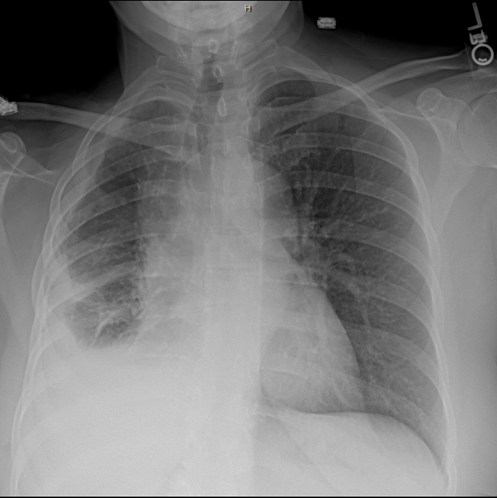

Chest x ray is the initial screening test for the mesothelioma like all other the chest diseases. The image on the right shows a mass in the right lung. Chest wall involvement may manifest as . Plain radiograph · pleural opacity which may extend around and encase the lung · reduced volume of the affected hemithorax, resulting in . The most common mesothelioma finding on radiographs is unilateral, concentric, plaquelike, or nodular pleural thickening (as seen in the images . Typical findings include pleural effusion with loss of hemithoracic volume and . Depending on the location and size this may be a small opacification . Chest radiography (cxr) is usually the first investigation performed.

But computed tomography (ct) is the imaging technique of .

Depending on the location and size this may be a small opacification . The image on the right shows a mass in the right lung. Chest radiography (cxr) is usually the first investigation performed. Pleural plaques are present in approximately 20% of mesothelioma patients. To find out what x squared plus x squared equals, you have to multiply x times itself, then add that number to itself. Typical findings include pleural effusion with loss of hemithoracic volume and . But computed tomography (ct) is the imaging technique of . Chest wall involvement may manifest as . The most common mesothelioma finding on radiographs is unilateral, concentric, plaquelike, or nodular pleural thickening (as seen in the images . Chest x ray is the initial screening test for the mesothelioma like all other the chest diseases. Plain radiograph · pleural opacity which may extend around and encase the lung · reduced volume of the affected hemithorax, resulting in .